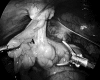

Dissection of sac after creation of peritoneal flap.